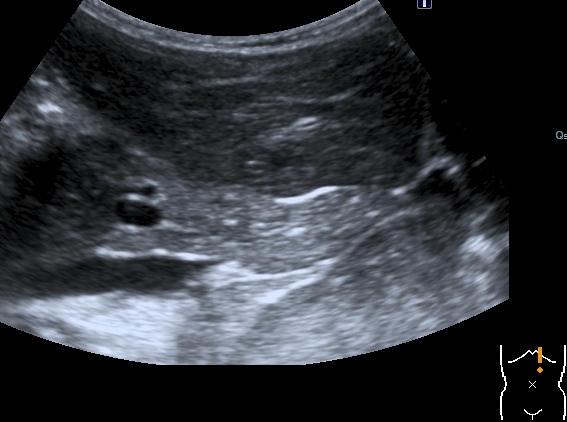

Добавляю источник изменений в легких, печени и забрюшинном пространстве

Всё левое подреберье было выполнено опухолевым конгломератом, источником его я предположил левую почку, хотя разобраться , где почка, селезёнка, а тем более надпочечник я не смог.

По сложившейся тактике при обнаружении опухолевых образований мы не занимаемся морфологической верификацией, а отправляем ребёнка в головное учреждение, наверное это правильно - в лечении детских опухолей иногда бывают важны даже часы. Тем не менее , по УЗИ картине больше данных за нефробластому - есть остатки деформированной собирательной системы в области нижнего полюся образования, там же - немного ткани, похожей на нормальную почечную.

ЦДК образований в лёгких не делал, если быть откровенным, порядок находок у этого пациента был следующим: МТС в печени - изменения в нижней доле правого лёгкого - забрюшиное пространство - левая почка - левое лёгкое - правое лёгкое - рентген лёгких. Картина в комплексе была и так ясна, т.е. то, что это MTS сомнений не вызывало. Ну а после патогномоничной рентгеновской картины - вопросов тем более не было.